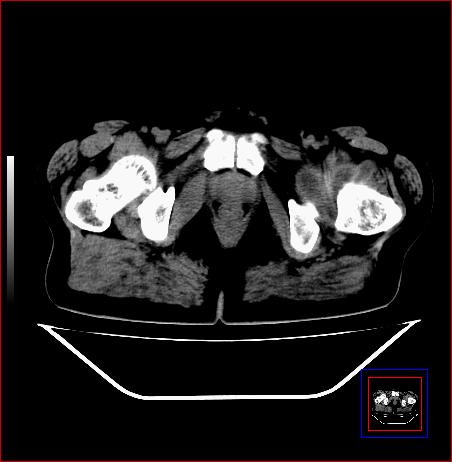

标题: CT15143:髋关节结核?

男,49,髋关节疼痛1年,无肺结核。

支持左侧髋关节结核合并轻度半脱位

骨质破坏,硬化,周围软组织脓肿,支持骨结核

骨质破坏,硬化,周围软组织脓肿,关节间隙增宽,支持骨结核

骨质破坏,硬化,周围软组织脓肿,关节间隙增宽,支持骨结核 .应与无菌坏死鉴别

支持:左侧髋关节结核合并轻度半脱位!

可以是结核,也可以是无菌坏死,还可以是先天髋关节脱位,不结合临床病史,只凭图像鉴别,请各位老师指教。

支持 左侧髋关节结核并半脱位。